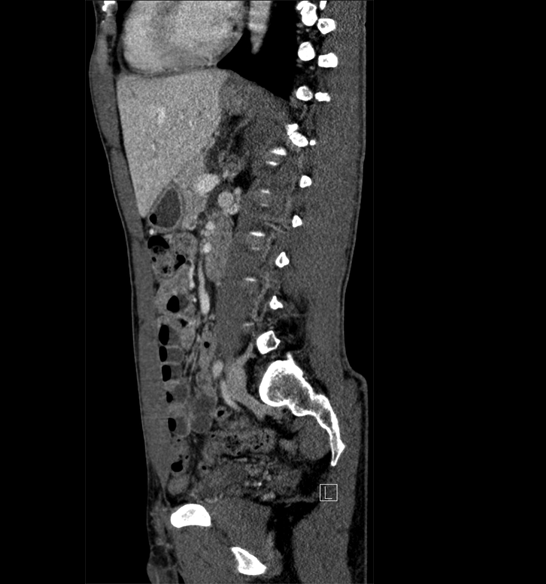

Body

Covers abdominal CT anatomy.